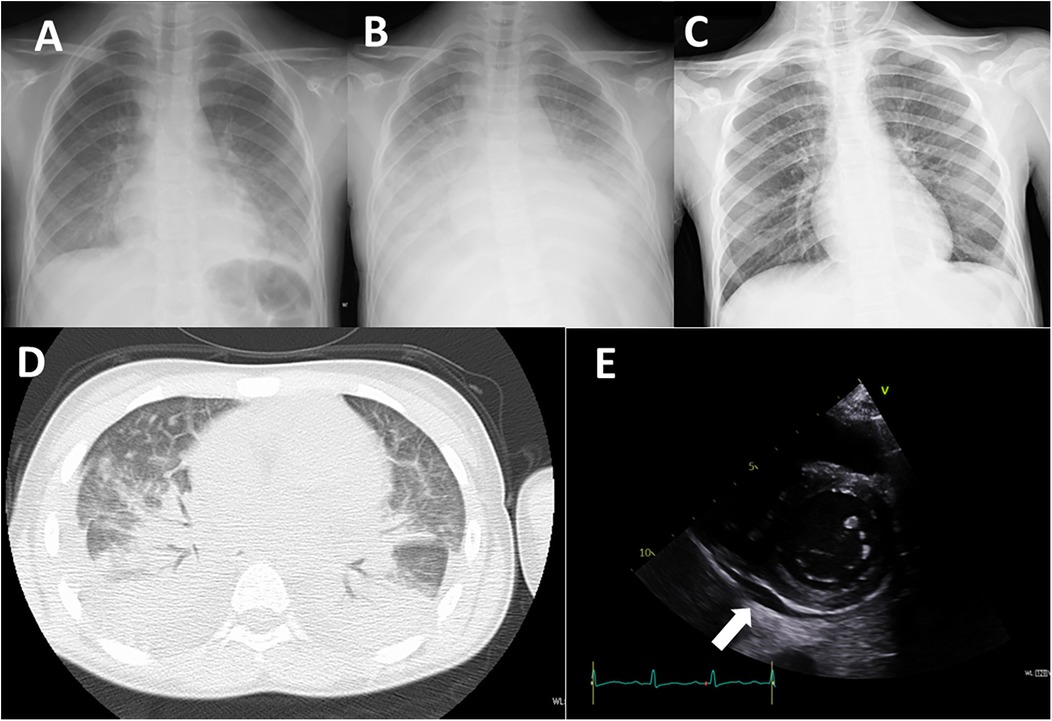

A 12-year-old girl had been aware of bilateral neck pain for 3 weeks prior to her first visit to the hospital. She had a fever over 38.0°C for 1 week before the visit. She was diagnosed as having cervical pyogenic lymphadenitis and was referred and admitted to the previous hospital. After starting intravenous antibiotics, she developed dyspnea and cough in addition to bilateral conjunctivitis, facial edema, and erythema on both cheeks. Her extremities had also appeared edematous. The dyspnea and cough rapidly worsened and a chest x-ray demonstrated massive plural effusions bilaterally (Figure 1).

Figure 1. Imaging studies. (A) Chest x-ray on admission to the previous hospital. (B) Chest x-ray on admission to our hospital (day 7 of illness). (C) Chest x-ray on day 12 of treatment (day 19 of illness). (D) Chest CT image on admission to our hospital (day 7 of illness). E: Echocardiography on admission to our hospital (day 7 of illness). Arrow indicates pericardial effusion.

On admission, her oxygen saturation was under 90% on room air. She had a respiratory rate of over 40 breath/min, heart rate 120 bpm, body temperature 37.5°C, blood pressure 99/52 mmHg, and body weight 32.6 kg (compared with 28.0 kg 1 month earlier). Oxygen saturation increased to 98% under oxygenation. On physical examination, she had an erythematous rash on both cheeks with no rash on the nose, inconsistent with butterfly rash observed in systemic lupus erythematosus. The abdomen was diffusely tender to palpation. Neither splenomegaly nor hepatomegaly were observed. Initial laboratory investigations revealed a white blood cell count of 5.8 × 109/L (normal 3.8–10.1 × 109/L), hemoglobin 9.7 g/dl (normal 11.9–14.9 g/dl), platelet count 75 × 109/L (normal 180–440 × 109/L), C-reactive protein level 149 mg/L (normal ≤3 mg/L), ferritin 2,439 ng/mL (normal 4.0–64.2 ng/mL), fibrinogen 446 mg/dl (normal 181–378 mg/dl), serum albumin 1.9 g/dl (normal 3.8–4.7 g/dl), serum aspartate aminotransferase 73 U/L (normal 15–30 U/L), alanine aminotransferase 64 U/L (normal 9–28 U/L), serum creatinine 0.36 mg/dl (normal 0.39–0.69 mg/dl), serum triglyceride 222 mg/dl (normal 30–149 mg/dl), IgG 720 mg/dl (normal 790–1,800 mg/dl), C3 126 mg/dl (normal 73–138 mg/dl), C4 7 mg/dl (normal 11–31 mg/dl), CH50 35.7 mg/dl (normal 30–40 mg/dl), sIL-2R 4,960 U/mL (normal 121–613 U/mL), IL-6 265 pg/mL (normal ≤3 pg/mL, IL-18 1,784 pg/mL (normal 36–258  pg/mL), and brain natriuretic peptide (BNP) 685 pg/mL (normal ≤18.4 pg/mL). NK cell activity was 9%, and anti-nuclear antibody was negative. A chest x-ray showed decreased transparency in both lung fields (Figure 1B). An echocardiographic study showed slight pericardial effusion and a normal cardiac ejection fraction (Figure 1E). A chest CT demonstrated massive plural effusions bilaterally (Figure 1D). Bone marrow aspiration performed on the third day of hospitalization revealed mild macrophage activation and hemophagocytosis. No significant bacterial growth was detected in standard microbiological cultures, including blood, sputum, and stool cultures. Serological testing for viral infections, potentially those associated with secondary HLH, such as Epstein–Barr virus, cytomegalovirus, and parvovirus B19, revealed a non-infectious profile, characterized by negative IgM antibodies.